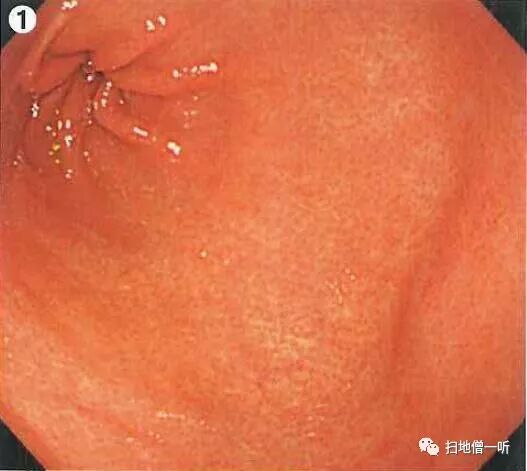

A:胃癌在图2。HP未感染胃癌。

整体胃粘膜光滑,未见明确萎缩。白光下可见无数小红点规则排列(RAC),所见为HP未感染征像。

接近观察及NBI非放大观察可见粘膜呈退色调改变,靛胭脂染色后界限不清。未分化癌初期可呈IIb表现,随着肿瘤进展可出现凹陷。本院数据显示当肿瘤小于10mm时 IIb36%,IIc64%;肿瘤11mm-20mm时 IIb6%,IIc94%

最终诊断:胃窦前壁,O-IIb,3mm,sig,T1a(M),UL(-)

小结:RAC提示HP阴性

HP阴性需要注意寻找未分化癌

未分化癌以退色调多见

初期未分化癌可只出现色调变化而不伴随凸凹变化